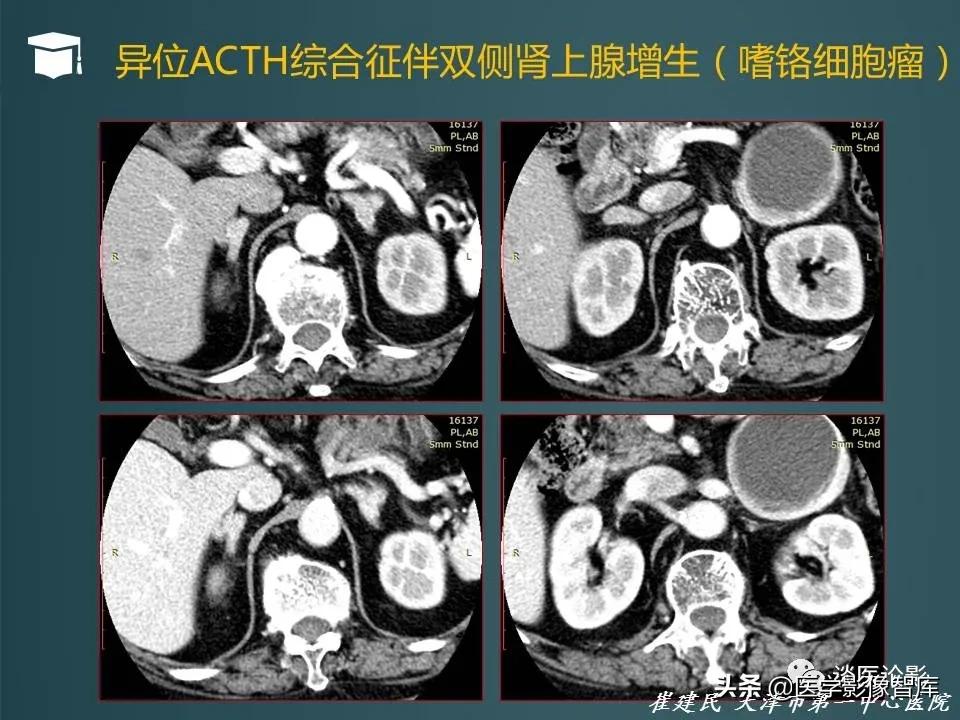

- 真性库欣病可以通过地塞米松抑制试验验证,小剂量地米抑制试验不被抑制,大剂量地米抑制试验被抑制即可证明为垂体性ACTH增高

- 小剂量地塞米松实验鉴别单纯性肥胖和库欣综合征,大剂量地塞米松实验鉴别垂体腺瘤和异位ACTH分泌综合征